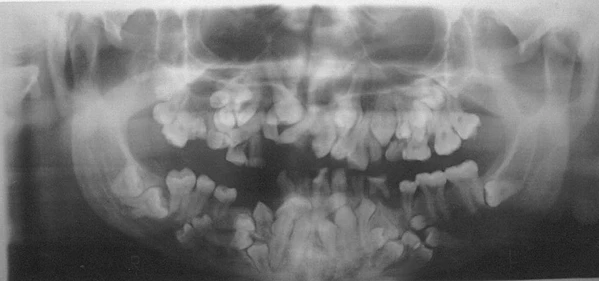

- Нарушения формирования корней, задержка в прорезывании молочных и постоянных зубов. Могут до 25-30-летнего возраста не меняться молочные зубы. Часто встречаются сверхкомплектные зубы.

Диагностика ключично-черепного дизостоза основана на клинических симптомах и рентгенологических исследованиях, которые включают изображения черепа, грудной клетки, таза и рук.

Заболевание в целом неизлечимо. Но чаще всего необходимо лечение проблем зубов, как наиболее значимых, причём начинать надо с детского возраста:

- Удаление молочных зубов.

- Удаление сверхкомплектных зубов.

- Ортодонтическое лечение.